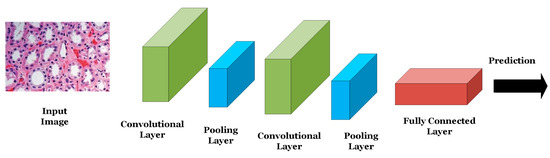

ANNs are used for classifying or analyzing one-dimensional signals such as speech or EEG signals. The nodes of the network are fully connected and the connections between the nodes are strengthened or weakened using weights updated via the backpropagation algorithm. CNNs are other forms of neural networks that are useful for handling two-dimensional as well as multi-dimensional signals such as digital images and videos. The main advantage of CNNs over ANNs is that CNNs are scalable where the number of learning parameters is independent on the input data size. As shown in Figure 2, CNNs consist mainly of convolutional layers that extract low- or high-level features from different regions of the image. Pooling layers are used to reduce the dimensionality of the extracted features by the convolutional layers and hence reduce the computational complexity of the network. Fully connected layers are deployed at the end of the network for the purpose of classifying the input based on the features generated by the convolutional and pooling layers.

Figure 2.

An example of a CNN.

LeNet was the first successful CNN introduced by LeCun et al. in 1989 to classify and identify handwritten numbers in 28 × 28 images of the MINIST dataset [7]. LeNet consists of two convolutional layers, where each is succeeded by a pooling layer and three fully connected layers. Following the success of the LeNet, AlexNet was introduced in 2012 by Krizhevsky et al. [8] to classify a subset of the ImageNet dataset consisting of almost 1.2 million images belonging to 1000 different classes at a top-5 error of 15.3%. AlexNet consists mainly of five convolutional layers and three fully connected layers. Due to the relatively large size of the network, data augmentation as well as drop out operations (i.e., dropping or turning off a certain number of neurons in the network during the training process of the model) were adopted to reduce model overfitting. In 2014, Google researchers introduced the GoogleNet/Inception network consisting of 22 layers including convolutional, pooling, and fully connected layers and achieving a top-5 error of 6.67% in classifying the ImageNet dataset (i.e., 8.63% improvement over the accuracy achieved by AlexNet with the same dataset) [9].

In the same year, the Visual Geometry Group Network (VGGNet) consisting of 16 convolutional layers was introduced and achieved a top-5 error of 7.3% using the same ImageNet dataset [10]. In 2015, the Residual Neural Network (ResNet) with 152 layers was introduced by He et al. achieving a top-5 error of 3.57% with the ImageNet dataset [11]. This network introduced the concept of skip connections where the output of one layer can be connected to latter layers of the network bypassing several layers. Due to the relatively high accuracy of the VGGNet and ResNet networks, the models have been widely adopted in many medical applications including PD screening and staging where the models that have been pre-trained on the ImageNet dataset were then fine-tuned on the PD datasets. This transfer of knowledge from a computer vision application (i.e., ImageNet dataset) to a medical application is called transfer learning.